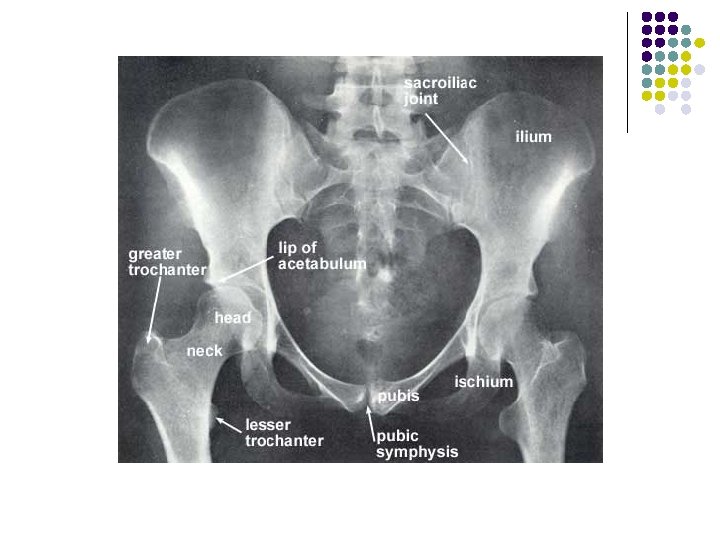

Bones Of The Gluteal Region Hip bone 1. 2. 3. l l Meet one another at the acetabulum Articulate with the sacrum at the sacroiliac joints l l The ilium The ischium The pubis Form the anterolateral walls of the pelvis Articulate with one another anteriorly at the symphysis pubis.

The pubis l Divided into: l l l A body A superior ramus An inferior ramus l The bodies of the two pubic bones articulate with each other in the midline anteriorly at the symphysis pubis l The superior ramus joins the ilium and ischium at the acetabulum l The inferior ramus joins the ischial ramus below the obturator foramen. l The obturator foramen in life is filled in by the obturator membrane l The pubic crest forms the upper border of the body of the pubis, and it ends laterally as the pubic tubercle

The Acetabulum l l l On the outer surface of the hip bone is a deep depression, called the acetabulum Articulates with the head of the femur to form the hip joint The inferior margin of the acetabulum is deficient and is marked by the acetabular notch The articular surface of the acetabulum is limited to a horseshoe shaped area and is covered with hyaline cartilage. The floor of the acetabulum is non-articular and is called the acetabular fossa

Femur l l Articulates above with the acetabulum and below with the tibia and the patella The upper end of the femur has l l A head A neck Greater and lesser trochanters The head forms about two thirds of a sphere l Articulates with the acetabulum of the hip bone to form the hip joint